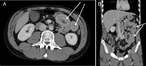

Multiple intestinal intussusceptions caused by highly impaired gastrointestinal motility in a patient with chronic cannabis consumption

Olga Prokopchuk and others

Journal of Surgical Case Reports, Volume 2019, Issue 5, May 2019, rjz160, https://doi.org/10.1093/jscr/rjz160